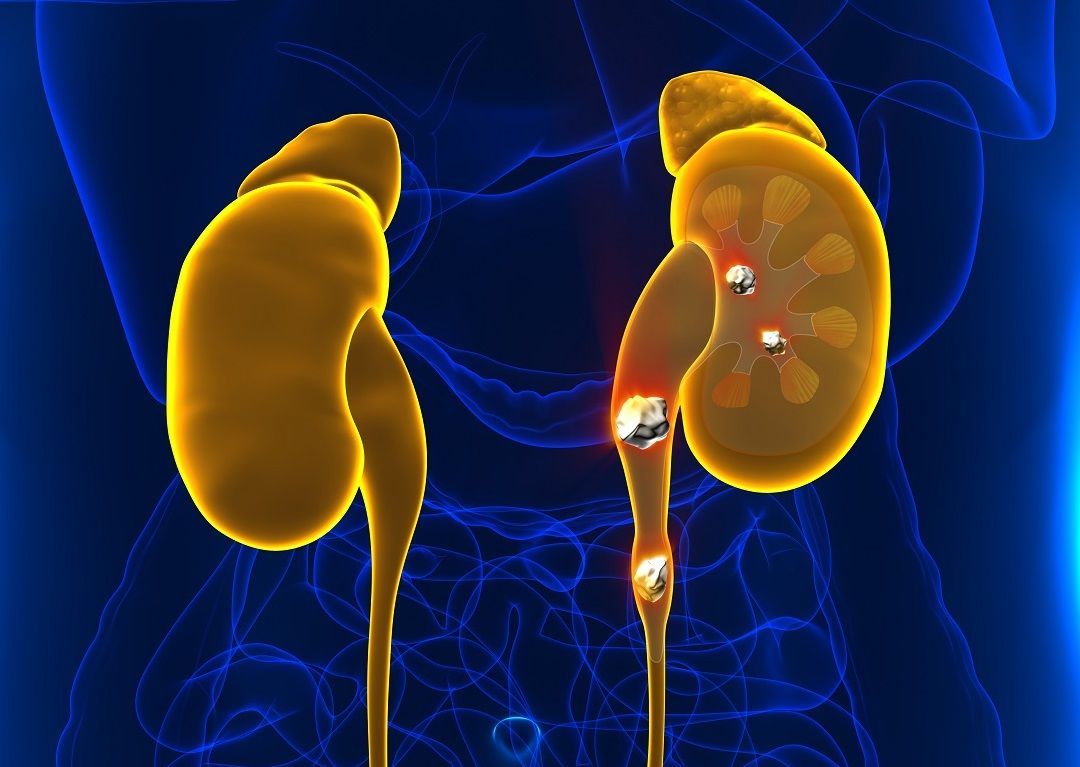

Οι λίθοι (πέτρες) στα νεφρά είναι εναποθέσεις από μεταλλικά ιχνοστοιχεία και άλατα που σχηματίζονται μέσα σε αυτά.

Στις αιτίες σχηματισμού τους περιλαμβάνονται η διατροφή, το υπερβολικό σωματικό βάρος, ορισμένες παθήσεις και κάποια συμπληρώματα και φάρμακα.

Συχνά, σχηματίζονται όταν τα ούρα λιμνάζουν, επιτρέποντας στα ιχνοστοιχεία να κρυσταλλώσουν και να κολλήσουν μεταξύ τους.

Μια πέτρα στο νεφρό συνήθως δεν προκαλεί συμπτώματα μέχρι να μετακινηθεί μέσα σε αυτό ή να περάσει στους ουρητήρες, τους σωλήνες που συνδέουν τα νεφρά και την ουροδόχο κύστη.

Η διέλευση μπορεί να είναι αρκετά επώδυνη (κολικός νεφρού), αλλά οι πέτρες συνήθως δεν προκαλούν μόνιμη βλάβη, εάν ανιχνευθούν έγκαιρα.

Τύποι λίθων στα νεφρά

Οι τύποι λίθων στα νεφρά περιλαμβάνουν:

• Πέτρες ασβεστίου. Οι περισσότερες πέτρες στα νεφρά είναι πέτρες ασβεστίου, συνήθως με τη μορφή οξαλικού ασβεστίου

• Πέτρες στρουβίτη, που σχηματίζονται ως αντίδραση στην ουρολοίμωξη

• Πέτρες ουρικού οξέος

• Πέτρες κυστίνης

Συμπτώματα

Όταν μια πέτρα στα νεφρά προκαλεί συμπτώματα, αυτά περιλαμβάνουν:

• Έντονο, οξύ πόνο στο πλάι και στην πλάτη, κάτω από τα πλευρά

• Πόνο που ακτινοβολεί στην κάτω κοιλιακή και στη βουβωνική χώρα

• Πόνο που έρχεται σε κύματα και αυξομειώνεται σε ένταση

• Πόνο ή αίσθημα καύσου κατά την ούρηση

• Ούρα ροζ, κόκκινα ή καφέ

• Ούρα θολά ή δύσοσμα

• Επίμονη ανάγκη για ούρηση, ούρηση συχνότερα από το συνηθισμένο ή ούρηση σε μικρές ποσότητες

• Ναυτία και έμετο

• Πυρετό και ρίγη, εάν υπάρχει μόλυνση

Παράγοντες κινδύνου

Οι παράγοντες που αυξάνουν τον κίνδυνο εμφάνισης λίθων στα νεφρά περιλαμβάνουν:

• Οικογενειακό ή προσωπικό ιστορικό

Εάν κάποιος στην οικογένειά σας είχε πέτρες στα νεφρά, είναι πιο πιθανό να αναπτύξετε πέτρες.

• Αφυδάτωση

Το να μην πίνετε αρκετό νερό κάθε μέρα μπορεί να αυξήσει τον κίνδυνο δημιουργίας πέτρας στα νεφρά. Οι άνθρωποι που ζουν σε ζεστά, ξηρά κλίματα και όσοι ιδρώνουν πολύ μπορεί να διατρέχουν μεγαλύτερο κίνδυνο από άλλους.

• Ορισμένες δίαιτες

Η διατροφή με υψηλή περιεκτικότητα σε πρωτεΐνη, νάτριο (αλάτι) και ζάχαρη μπορεί να αυξήσει τον κίνδυνο εμφάνισης λίθων νεφρών.

• Παχυσαρκία

• Ασθένειες του πεπτικού και χειρουργικές επεμβάσεις σε αυτό.

• Άλλες ιατρικές καταστάσεις, όπως νεφρική σωληναριακή οξέωση, κυστινουρία, υπερπαραθυρεοειδισμός και επαναλαμβανόμενες λοιμώξεις του ουροποιητικού συστήματος.

• Ορισμένα συμπληρώματα και φάρμακα (όπως βιταμίνη C, συμπληρώματα διατροφής, καθαρτικά), αντιόξινα με βάση το ασβέστιο και ορισμένα φάρμακα που χρησιμοποιούνται για τη θεραπεία ημικρανιών ή κατάθλιψης.

Πρόληψη

Η πρόληψη περιλαμβάνει αλλαγές στον τρόπο ζωής όπως:

Καλή ενυδάτωση (8 ποτήρια νερό την ημέρα)

Λιγότερα τρόφιμα πλούσια σε οξαλικά όπως παντζάρια, μπάμιες, σπανάκι, γλυκοπατάτες, ξηρούς καρπούς, τσάι, σοκολάτα, μαύρο πιπέρι και προϊόντα σόγιας

Λιγότερο αλάτι και ζωικές πρωτεΐνες

Τροφές πλούσιες σε ασβέστιο που δεν επηρεάζουν τον κίνδυνο δημιουργίας λίθων στα νεφρά